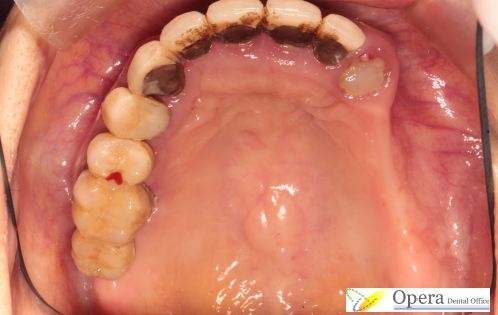

上あごの咬合面観です

咬合面観の解説です。残せる歯は3本しかありません。

保健の入れ歯はすべてプラスチックで作るため、天井をすべて覆わなければすぐに割れてしまいます。

そもそも部分入れ歯は学問として考えるならば必ず金属床で作らなければなりません。